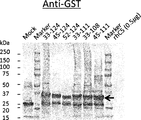

- Figure 3 illustrates Western Blot analysis against C5 beta-chain-derived fragments (amino acids 19-180, 161-340, 321-500, and 481-660 of SEQ ID NO:40) fused to GST-tag, as described in Example 4.1.

- CFA0305, CFA0307, CFA0366, CFA0501, CFA0538, CFA0599, CFA0666, CFA0672, and CFA0675 are antibodies grouped into epitope C.

- Anti-GST antibody is a positive control.

- the position of the GST-fused C5 fragments (46-49 kDa) is marked with an arrow.